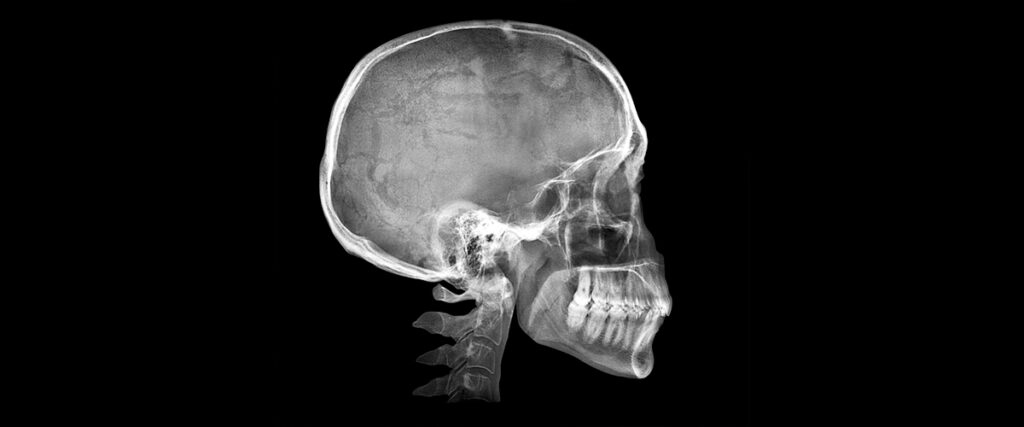

La telerradiografía lateral de cráneo es un tipo específico de radiografía que muestra una imagen precisa y detallada de la cabeza vista desde un lado (lateralmente). Se realiza con el paciente en posición erguida, de pie o sentado, manteniendo una postura natural con los dientes juntos.

Se le llama telerradiografía porque la imagen se toma desde una distancia fija, generalmente alrededor de 1,5 metros, con el fin de reducir al mínimo cualquier posible distorsión o ampliación. El resultado es una radiografía muy precisa, exacta y reproducible, lo que permite realizar mediciones fiables para analizar el perfil facial y dental del paciente.

A diferencia de otras radiografías más comunes, la telerradiografía lateral de cráneo permite ver claramente:

- Huesos craneales y faciales: Se observa fácilmente la posición de la mandíbula, el maxilar superior, la base del cráneo y la estructura ósea completa del rostro.

- Relación entre los maxilares: Podemos identificar si existe alguna desproporción o desequilibrio entre el maxilar superior y la mandíbula (por ejemplo, mandíbula adelantada o retraída).

- Posición e inclinación de los dientes: Especialmente incisivos superiores e inferiores, evaluando si están inclinados hacia adelante o hacia atrás.

- Vías respiratorias superiores: Podemos visualizar el espacio disponible para el paso del aire, lo que ayuda a detectar problemas respiratorios o factores relacionados con ronquidos o apnea del sueño.

- Crecimiento craneofacial en niños y adolescentes: Facilita observar cómo están creciendo los huesos faciales, algo clave en tratamientos tempranos de ortodoncia.